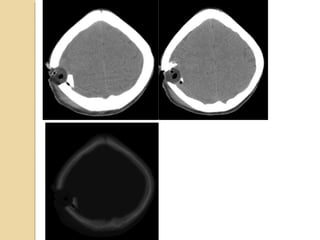

Skull FracturesSkull Fractures Thinskull #’s common place. Risk of # associated intracranial injuries? CT to R/o 1. Open 2. Closed 3. Comminuted 4. Diastatic 5. Depressed

SIGNIFICANT SKULL FRACTURESSIGNIFICANTSKULL FRACTURES “Depressed”: inner table is depressed by the thickness of the skull. Overlie major venous sinus, motor cortex, middle meningeal artery Pass through sinuses Look for sutural diastasis (lambdoid)

TEMPORAL BONE FRACTURESTEMPORALBONE FRACTURES Look for opacification of the mastoid Longitudinal: 70%, parallel to long axis of petrous bone, conductive hearing loss (from ossicular dislocation), facial nerve paralysis (20%) Transverse: 20%, sensorineural hearing loss, facial nerve paralysis (50%) Complex Complications: meningitis, abscess